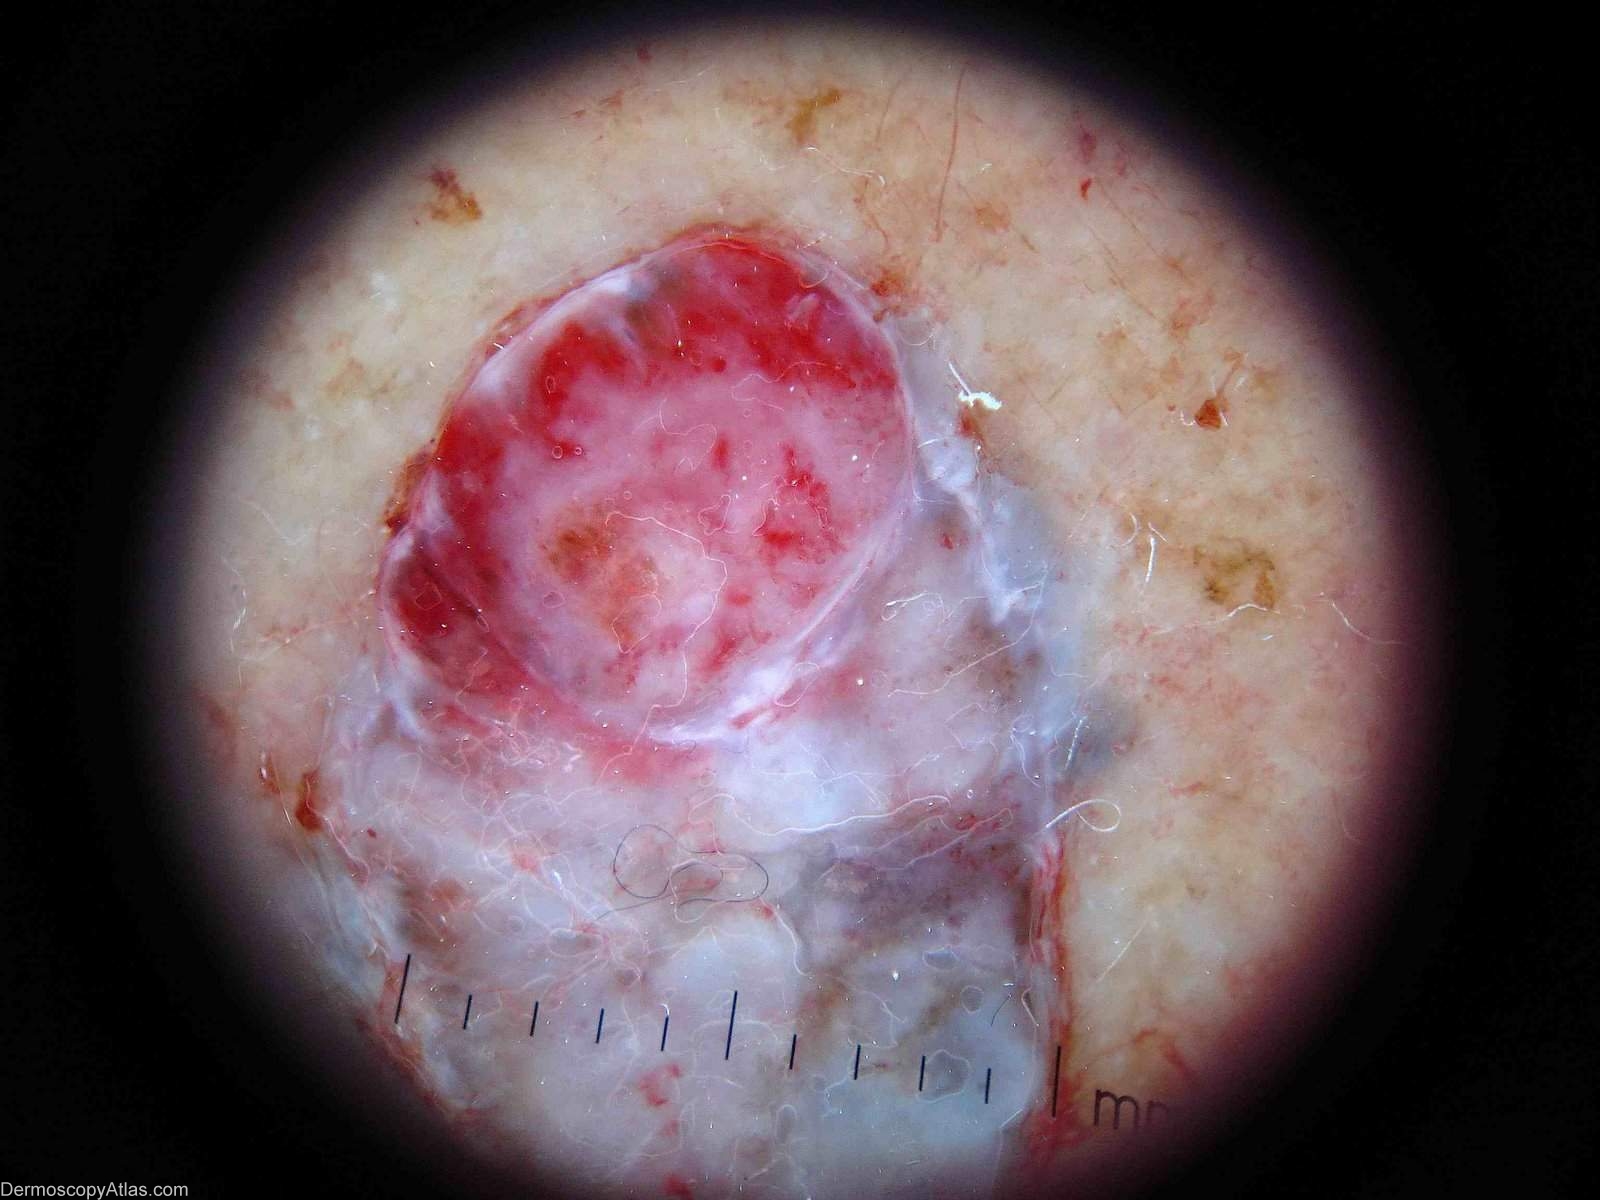

Site: Leg

Diagnosis: Pigmented basal cell carcinoma

Description: Dermatoscopy of blue nodule on leg. There are massive blue ovoid nests without a network.

Sometimes pigmented BCCs can look so blue they resemble melanomas. The other two images are courtesy of Dr Martin Baker illustrating the came point. These two are even more suggestive of malignant melanoma.